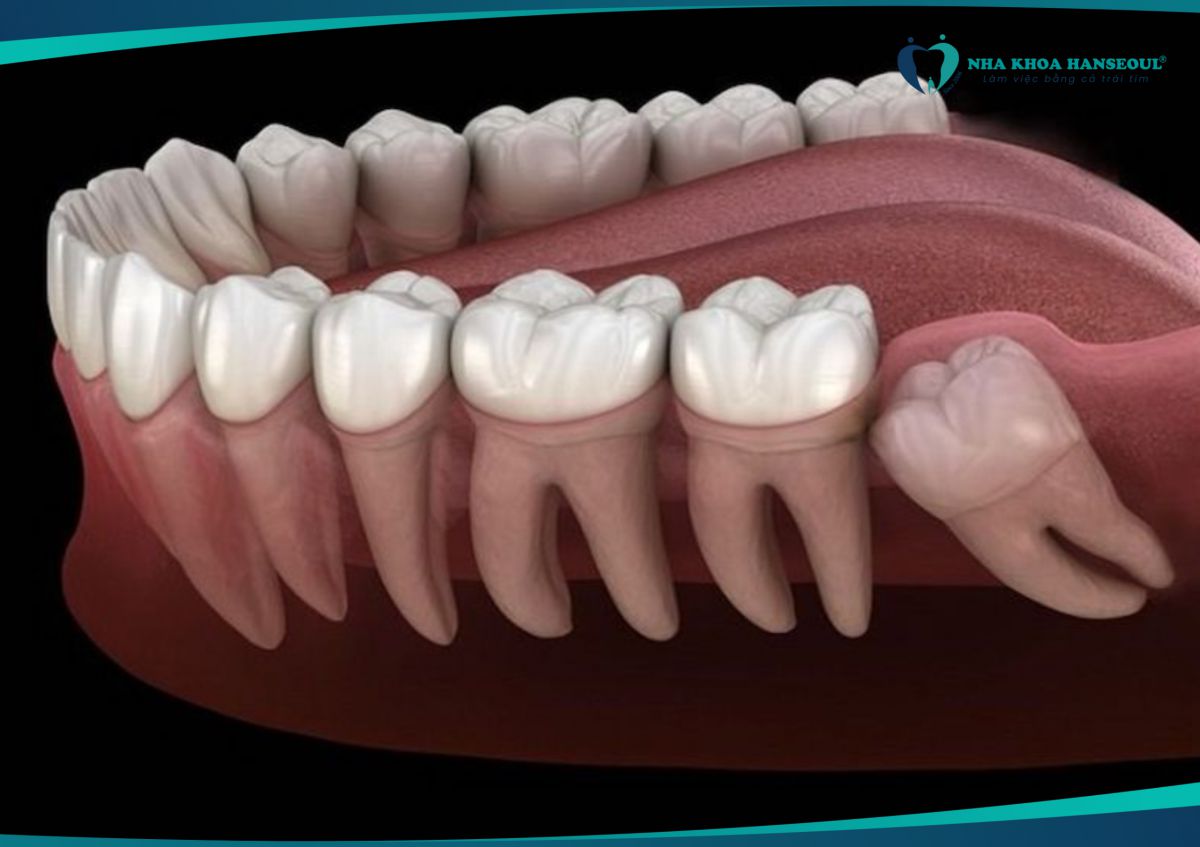

- Răng khôn mọc lệch có thể đẩy vào răng số 7, gây sâu răng, lung lay hoặc thậm chí mất răng vĩnh viễn.

- Nếu không điều trị sớm, bạn có thể phải nhổ cả hai răng.

7 Gây xô lệch cả hàm răng

- Răng khôn mọc lệch có thể làm thay đổi cấu trúc hàm, khiến các răng khác bị xô lệch, ảnh hưởng đến thẩm mỹ và chức năng nhai.